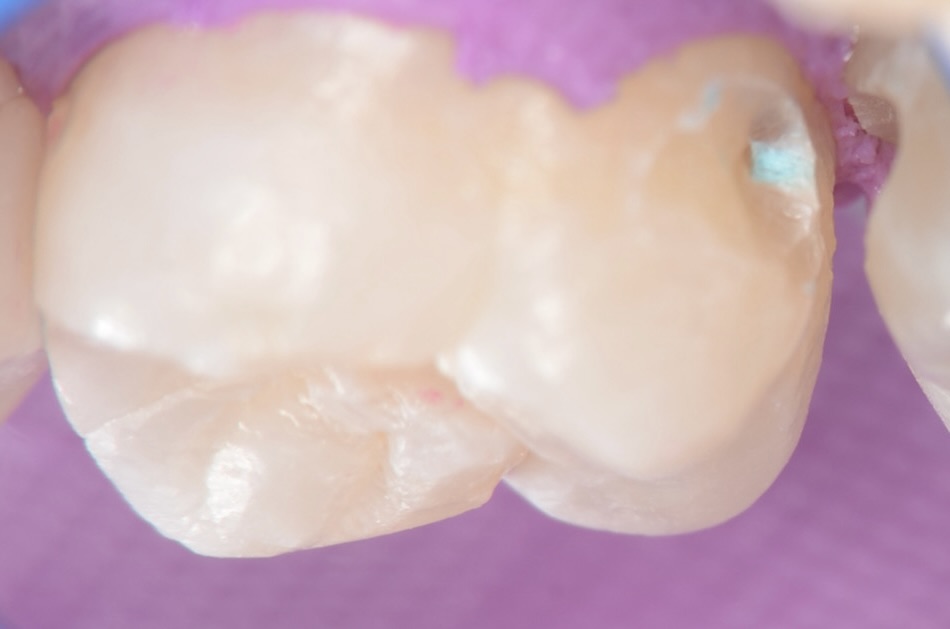

上顎7番頬側面観

歯ブラシがしにくい上の奥歯の横は、虫歯ができやすい場所でもあります。 -

かつてレジンで治療されている部分が虫歯になっています。 -